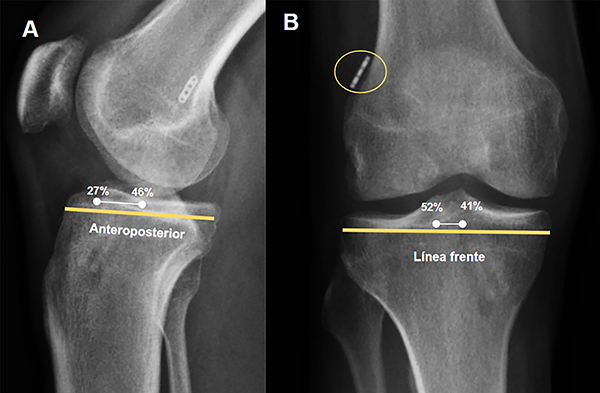

La posición ideal para la salida del túnel femoral es en el 35% de la línea vertical (28 a 43%), 0% es la cortical proximal, y un 29% en la línea de Blumensaat (rango 24 a 37%), siendo 0% la cortical posterior8 (fig. 1A). La posición del túnel tibial en la radiografía de perfil fue evaluada con la grilla de Stӓubli y Rauschning, la posición ideal para la salida del túnel tibial en la línea anteroposterior es en el 42% (rango 39 a 46%), considerando 0% la cortical anterior. En la radiografía de frente se evaluó la salida del túnel tibial en el platillo tibial de medial a lateral, la posición ideal de la salida del túnel es en el 48% (rango 41 a 52%), considerando 0% la cortical medial (fig. 1B). Finalmente, se evaluó la ubicación del botón cortical femoral, en relación a la cortical femoral, midiendo la interposición de partes blandas entre el botón y la cortical en milímetros.

El objetivo primario del presente estudio fue describir la ubicación de los túneles tibiales y femorales en pacientes operados de RLCA. La ubicación de la salida de los túneles se reportó como el porcentaje de las líneas radiográficas en el frente y en el perfil, ya sea tibial o femoral, en la cuales sale el túnel. En segundo lugar, evaluamos la proporción de pacientes que presentaron una salida correcta en relación a cada línea analizada. Se consideraron márgenes correctos para el fémur los siguientes: línea Blumensaat 24 a 37%, línea vertical 28% a 43%; para la radiografía de perfil tibial, línea anteroposterior 27 a 46% y en la línea radiografía tibial de frente la línea entre los platillos tibiales se consideró como correcta el túnel que sale entre el 41 a 52% de la línea. Las variables continuas se reportaron como media y desviación estándar o mediana e intervalo intercuartílico, según distribución. Las variables categóricas se reportaron como número absoluto, proporción y sus respectivos intervalos de confianza del 95% (calculados con la aproximación exacta).

Figura 2: Radiografía de perfil postoperatoria inmediata RLCA de rodilla izquierda en la que se pueden observar los túneles tibiales. A) Véase la línea tibial anteroposterior del perfil, donde la salida del túnel tibial idealmente tiene que estar al 42% de la línea (27 a 46%). B) Radiografía frente postoperatoria inmediata de rodilla izquierda donde se observa el botón de fijación cortical. Se concederá correcta colocación del botón si la distancia a la cortical es menor a 2 mm.